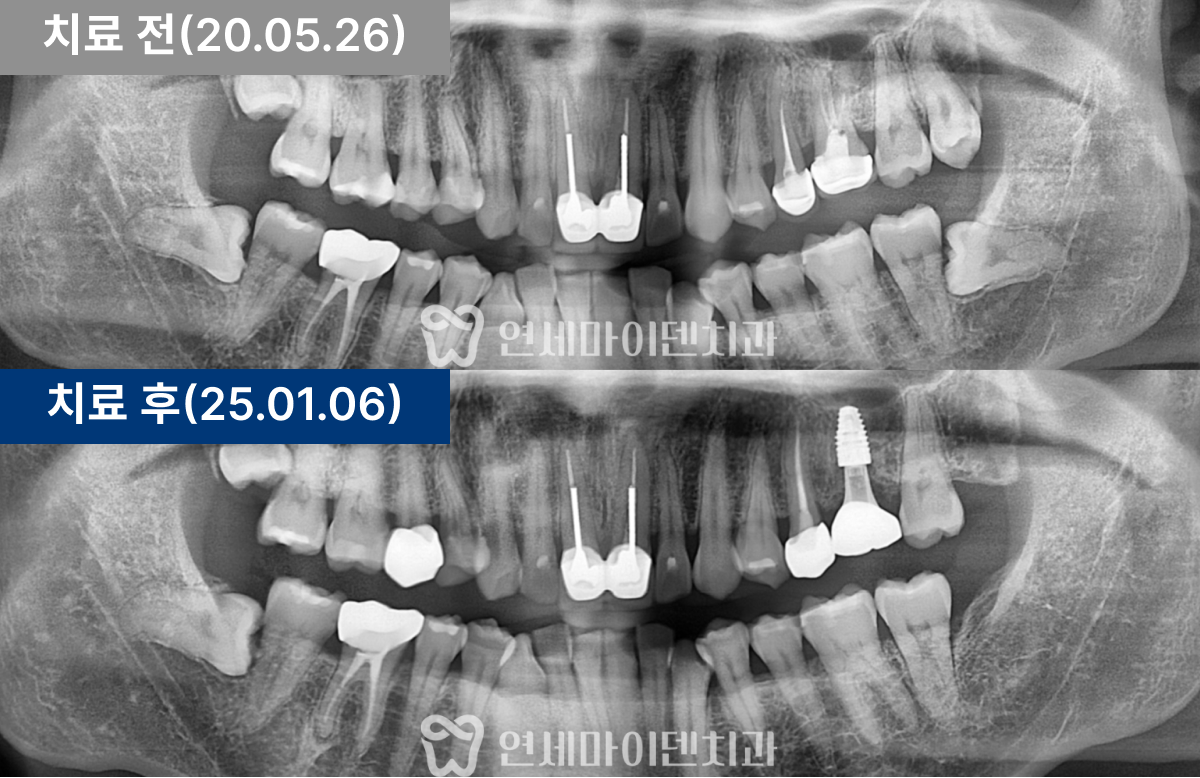

임플란트를 시행한 부위 잇몸이 잘 치유되었고, 3년 후까지의 경과 관찰에서 임플란트 부위가 안정적으로 유지되고 있었습니다. 환자분도 음식물 끼임 없이 편하게 사용 중이십니다.

앞쪽 치아의 뿌리끝 염증도 소실되었습니다. 염증이 사라졌다는 것은 뼈 재생이 이루어졌다는 의미로, 이 치아의 통증도 완전히 해소되어 잘 사용하고 계십니다.